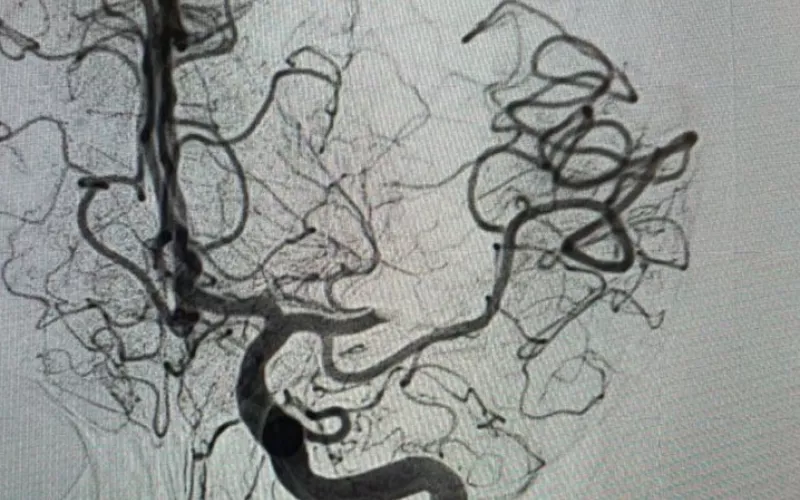

Mediante una resonancia magnética se le detectó la obstrucción de una arteria por un coágulo, fue identificada la zona afectada y se efectuó el rescate que consistió en introducir catéteres desde la ingle hasta el cerebro.

Con este procedimiento se logró que, de nueva cuenta haya circulación sanguínea hacia el cerebro de la derechohabiente; el lenguaje y el movimiento los recuperará paulatinamente conforme progrese con las sesiones de fisiatría, tratamiento farmacológico y cambios en el estilo de vida.